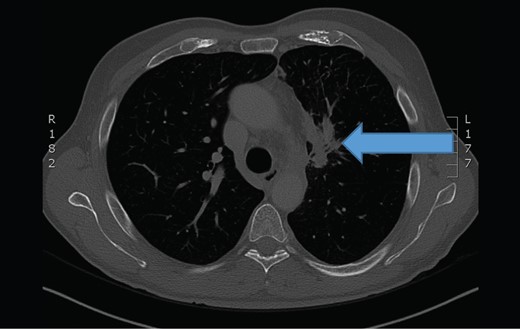

The chest computerized tomography scan showed a infiltrating tumor mass at the upper left lung (arrow).

Because of unknown origin of small intestinal metastases, the patient was referred to extensive diagnostics. Chest CT showed a large primary lung tumor in the left upper pulmonary lobe with pathological mediastinal lymph nodes. The patient was presented to multidisciplinary team and was later referred to oncology for further treatment.